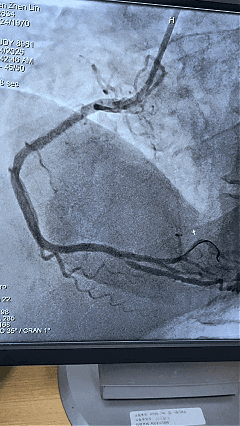

在控制住恶性心律失常后,患者被安全转运至导管室。由于病情危重,医院立即启动全院蓝色代码(医疗急救响应)。在急诊科、麻醉科、重症医学科(ICU) 的紧密护航下,心内科介入团队成功为患者完成了介入治疗,开通了闭塞血管。

影像图片